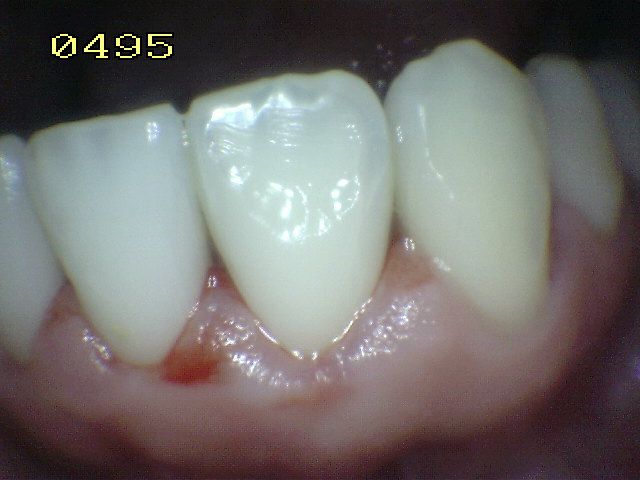

• Hacer examen visual de la superficie húmeda:

1. Inicie desde el cuadrante superior derecho del paciente

2. Prosiga con la orientación de las manecillas del reloj

3. Inicialmente el examen visual se realiza con las superficies húmedas.

• Secar con jeringa triple por 5 segundos para realizar el examen visual en seco